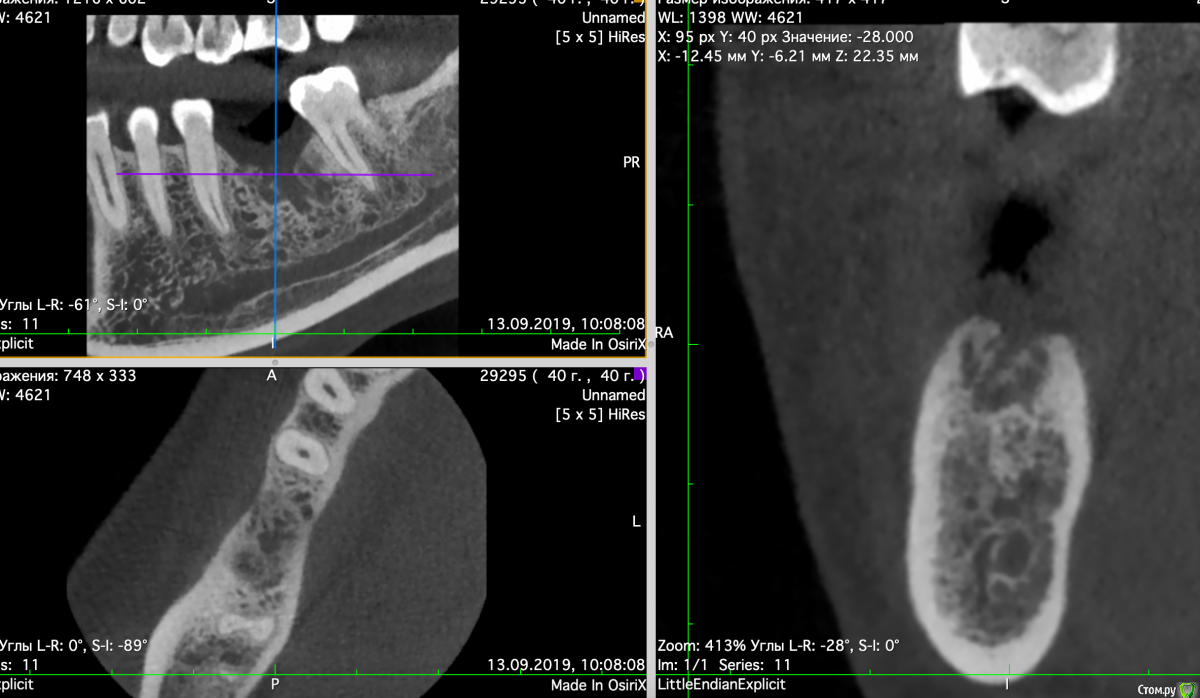

Valerkaa Опубликовано 13 сентября, 2019 Поделиться Опубликовано 13 сентября, 2019 Добрый день, коллеги. Помогите, пожалуйста, советом. Планируется имплантация, удаление было в феврале. Смущает состояние кости. Понятно, что можно раскрыться, и если грануляции, то кюретаж. Просто морально хочется понимать, чего ждать. Была ситуация, когда с похожей картиной на КТ раскрылась, кость была визуально норм, но через месяц имплант просто пинцетом достала.Собственно вопрос: нормальное ли это состояние кости через полгода после удаления или все-таки что-то не так и надо морально готовиться к кюретажу? Опыт в имплантации совсем небольшой, поэтому такие вопросы возникают)) Ссылка на комментарий

Евгений Ходыкин Опубликовано 13 сентября, 2019 Поделиться Опубликовано 13 сентября, 2019 Будет кюретаж, всё верно. 2 Ссылка на комментарий

dr Alexandr Опубликовано 14 сентября, 2019 Поделиться Опубликовано 14 сентября, 2019 Нужен кюретаж, что б потом не готовиться морально к удалению имплантанта!..подготовить кость и спланировать операцию, возможно понадобиться подсадка кости. Ссылка на комментарий